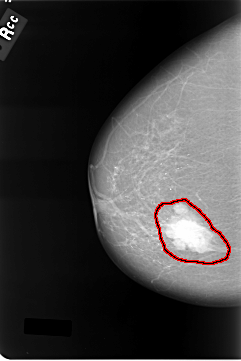

C_0011_1.RIGHT_CC

RIGHT_CC LINES 5768 PIXELS_PER_LINE 3848 BITS_PER_PIXEL 12 RESOLUTION 50 OVERLAY

FILE: C_0011_1.RIGHT_CC.OVERLAY

TOTAL_ABNORMALITIES 1

ABNORMALITY 1

LESION_TYPE MASS SHAPE LOBULATED MARGINS CIRCUMSCRIBED

ASSESSMENT 5

SUBTLETY 5

PATHOLOGY MALIGNANT

TOTAL_OUTLINES 1

BOUNDARY